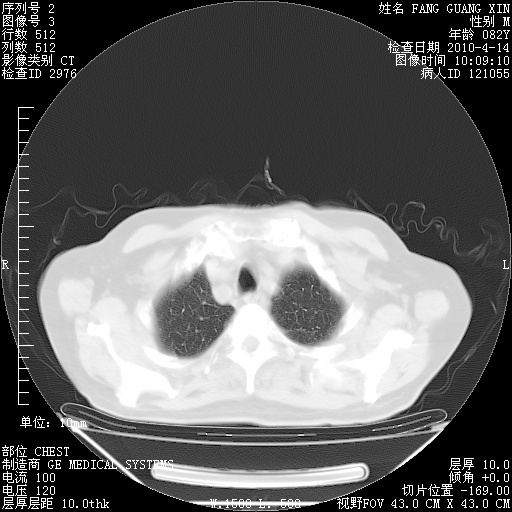

肺部CT平扫未见异常。